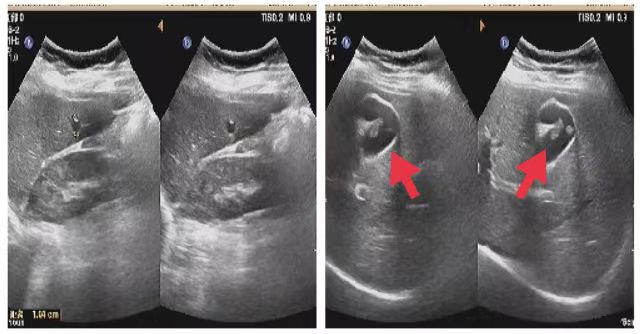

08、**女士,25岁

于2023年10月15日在邯郸仁泰西区体检,心脏彩超检查提示:前纵膈内囊性回声7.3cm*5.3cm,考虑纵膈囊肿,建议客户到三甲医院进一步检查。2023年10月25日跟踪回访,客户已在中心医院就诊,确诊纵膈囊肿拟手术治疗。